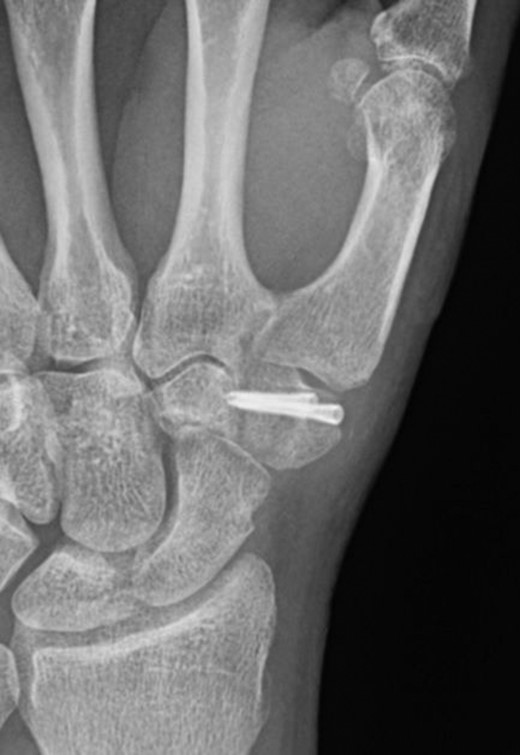

The CT scan (Fig. 2) showed a coronal fracture of the trapezium which was not united. At this stage the symptoms of pain and instability continued to persist and were preventing him returning to mountain biking. As the imaging also showed that there were no degenerative changes in either the trapezio-metacarpal joint or the scapho-trapezial joint, the decision was made to proceed with debridement of the non-union and rigid internal fixation.

The trapezium was exposed through a Wagner approach. Intra-operatively a coronal split of the trapezium was found with no evidence of union. The fracture site was debrided, reduced and fixed with two headless compression screws. The thumb was immobilized in a plaster following surgery. Six weeks following surgery plaster was removed and the patient started physiotherapy to regain range of movement and strength. His plain radiographs at this point showed progression to union.